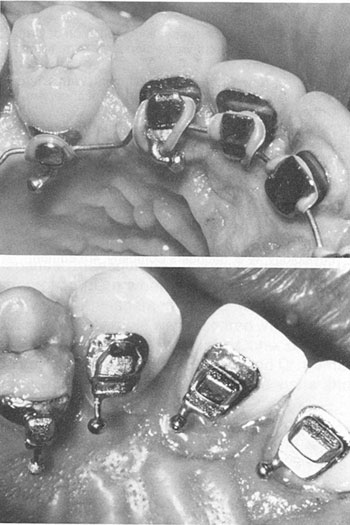

The Lingual Task Force was established in December 1980 to provide additional input on design considerations and to expand the treatment modalities. Ball hooks were added to all lingual brackets at this time. Ball hooks, while aiding greatly in placing elastic ligatures and elastics (Fig. 8), can cause gingival hyperplasia.

Fig. 6 Phase III Appliance (above) with flat bite wing on cuspid. Phase IV Appliance (below) with tapered cuspid bite plane.

Fig. 8 Ball hooks facilitate placement of elastic ligatures and intermaxillary elastics.